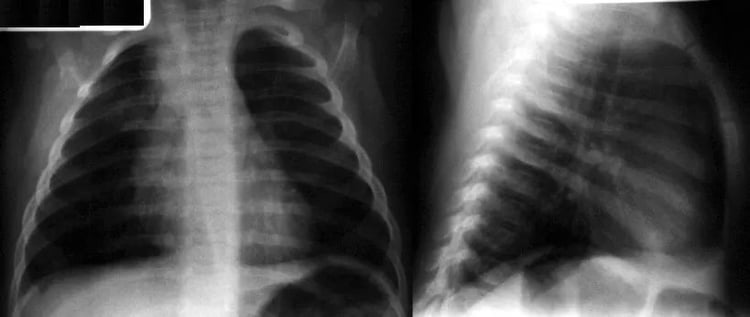

Most Missed Question in Pediatrics - Community-Acquired Pneumonia